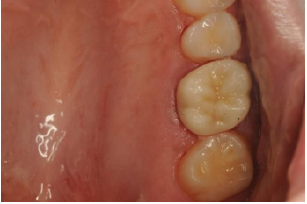

After six months recall, the tooth and the palatal mucosa area were asymptomatic and healthy. A full zirconia crown was cemented as final restoration. CBCT coronal view was evaluated showing palatal root end resection angulation and final restoration (Figure 6-8).

Figure 6: Six months after treatment the palatal surgical site was restored and a full zirconia crown was placed as final restoration.

Figure 7: Buccal view of maxillary first molar with full zirconia crown cemented.